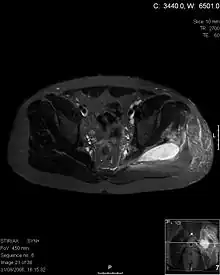

Diagnostic methodDiagnostic method used for PM includes ultrasound, CT scan and MRI. Ultrasound can be helpful in showing muscular heterogeneity or a purulent collection but it is not useful during the first stage of the disease. CT scan can confirm the diagnosis before abscesses occur with enlargement of the involved muscles and hypodensity when abscess is present, terogenous attenuation and fluid collection with rim enhancement can be found. MRI is useful to assess PM and determine its localization and extension

• MRI is useful